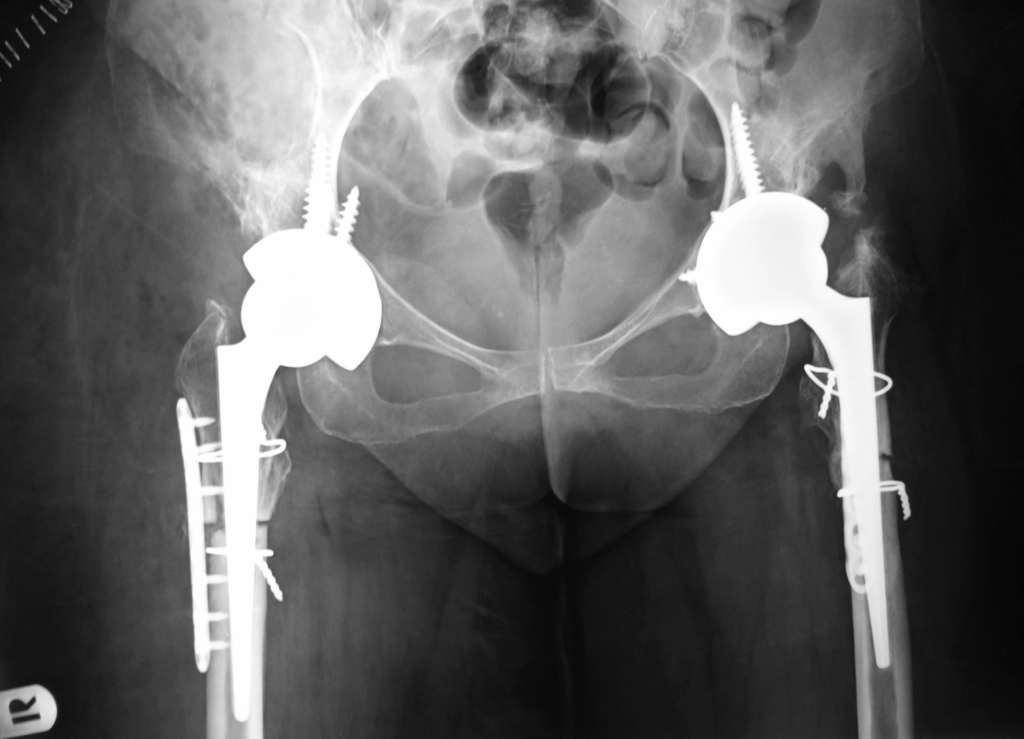

Υψηλό Συγγενές Εξάρθρημα του Ισχίου

To συγγενές εξάρθρημα του ίσχιου είναι μια κατάσταση όπου ο ασθενής γεννήθηκε με δυσπλασία και έκτοπη θέση της άρθρωσης του ισχίου. Μια παραμελημένη τέτοια κατάσταση που δεν αντιμετωπίστηκε στα πρώϊμα βρεφικά στάδια προκαλεί σημαντικά προβλήματα στην ενηλική ζωή.

Η εξειδικευμένη αντιμετώπιση της δυσπλασίας αυτής στους ενήλικες αποτελεί εξαιρετικά απαιτητική επέμβαση που λίγα κέντρα στην Ελλάδα και το εξωτερικό διαθέτουν σημαντική εμπειρία.